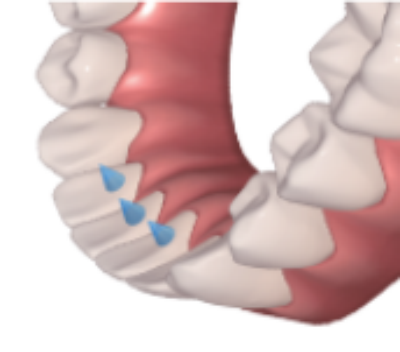

2. Mandibular Advancement

Solving the Problem of Small, Retracted Chin

Promote forward development of the mandibular bone, and improve the imbalance between the upper and lower jaws. At the same time, correct misaligned teeth, level the occlusal curve, and help achieve normal occlusion with a well-proportioned facial profile.